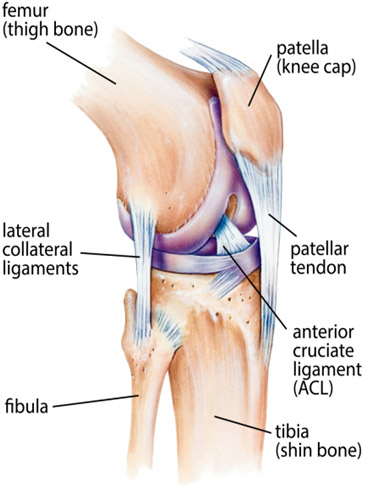

Our knee is one of the most complex and largest joints in the body. It connects our thigh bone (femur) to the shin bone (tibia).

Knee joint is responsible for bearing most of the weight of our body. So the main function of our knee is to act as a pivot/hinge letting our lower leg and foot to move, walk, swing, kick or run. The structure of the knee primarily consists of : bones, cartilages, tendons, ligaments, and a joint capsule.